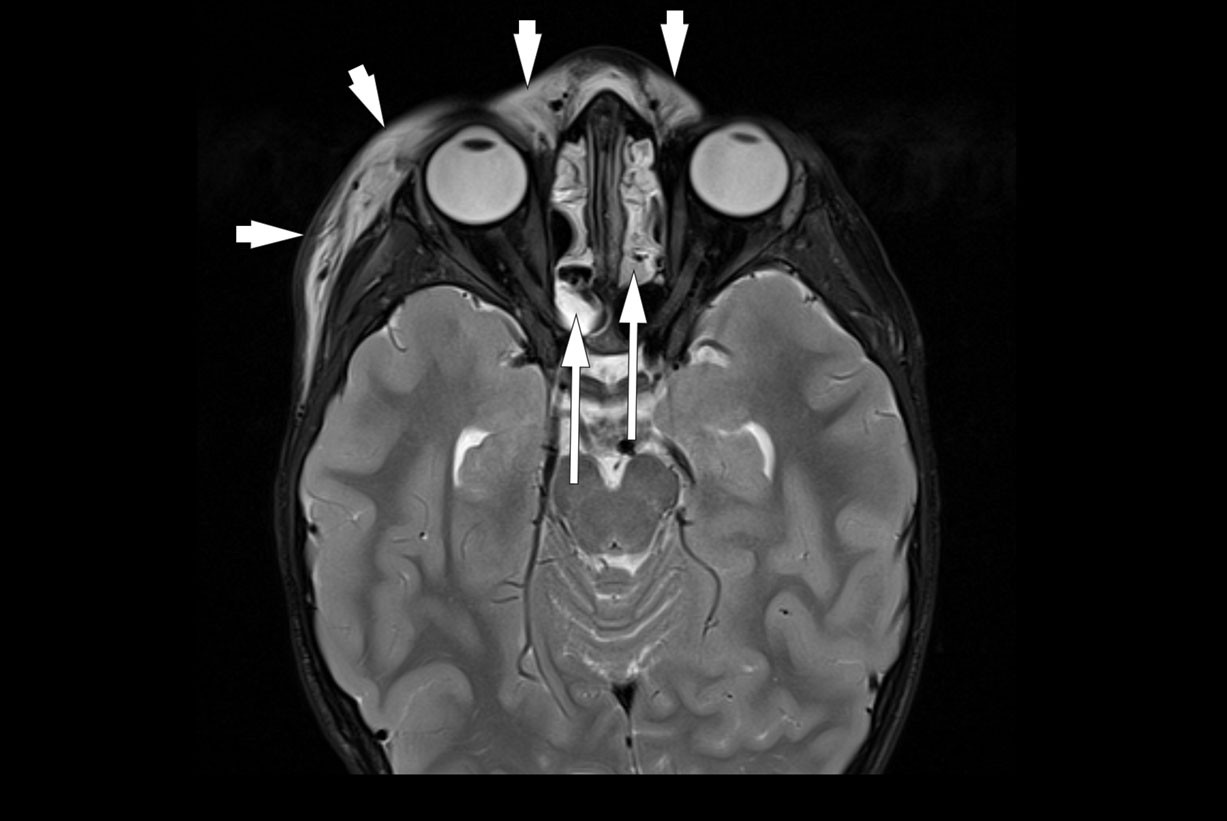

MR av bihuler, som ble rekvirert ved innkomst og tatt neste morgen, viste bilateral etmoiditt med høyresidig periorbital cellulitt, men ingen abscess (figur 1).